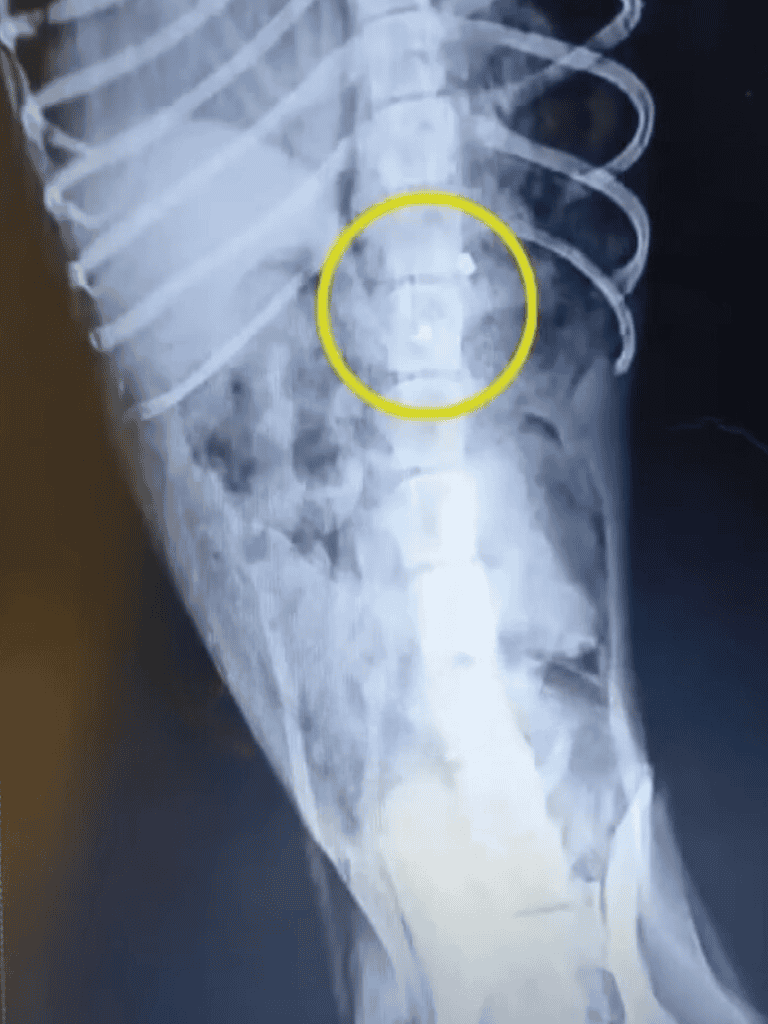

The X-rays revealed a grim reality: bullets had irreparably damaged his spine. As the seriousness of the situation set in, we quickly inserted a urinary catheter to prevent infections.

Fortunately, the bullets had been carefully extracted, leaving Teo a bit more at ease, though the spinal cord damage cast a heavy shadow over his prognosis.